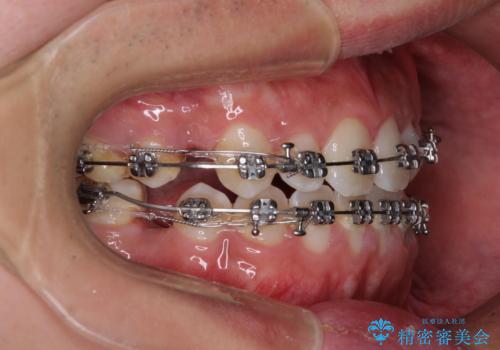

- メタルブラケット

奥歯の咬み合わせを改善させた後、上下左右の小臼歯(下顎は残存乳歯)を計4本抜歯し、ワイヤー装置にて口元の突出感を改善しながら咬み合わせを整えることとしました。

下顎の残存乳歯は小臼歯よりも大きいため、スペースを閉じるために長い期間を必要としますが、予想通りに長期間を要することとなりました。

受け口傾向の方の抜歯矯正は、下顎前歯が舌側に倒れることで歯肉退縮を起こしやすいことが知られていますが、ワイヤーに工夫をすることでリスクを軽減させています。